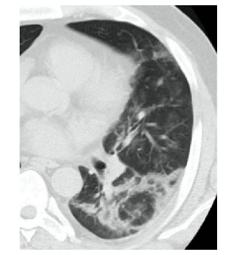

КТ имеет высокую чувствительность в выявлении изменений в легких, характерных для COVID-19. Применение КТ целесообразно для первичной оценки состояния ОГК у пациентов с тяжелыми прогрессирующими формами заболевания, а также для дифференциальной диагностики выявленных изменений и оценки динамики процесса. КТ позволяет выявить характерные изменения в легких у пациентов с COVID-19 еще до появления положительных лабораторных тестов на инфекцию с помощью МАНК. В то же время, КТ выявляет изменения легких у значительного числа пациентов с бессимптомной и легкой формами заболевания, которым не требуется госпитализация. Результаты КТ в этих случаях не влияют на тактику лечения и прогноз заболевания при наличии лабораторного подтверждения COVID-19. Поэтому массовое применение КТ для скрининга асимптомных и легких форм болезни не рекомендуется.

4. Все выявляемые при лучевых исследованиях признаки, включая КТ-симптомы, не являются специфичными для какого-либо вида инфекции и не позволяют установить этиологический диагноз. Вне клинической (эпидемической) ситуации они не позволяют отнести выявленные изменения к пневмонии COVID-19 и дифференцировать их с другими пневмониями и невоспалительными заболеваниями. Данные лучевого исследования не заменяют результаты обследования на РНК SARS-CoV-2. Отсутствие изменений при КТ не исключают наличие COVID-19 и возможность развития пневмонии после проведения исследования.